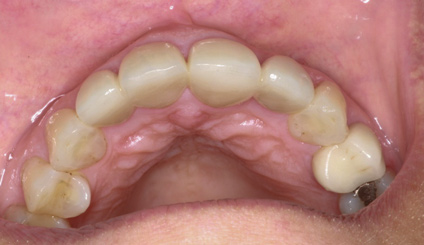

(6.) A 3-year, posttreatment photograph showing healthy tissue supporting the maxillary anterior teeth and correction of crowding.

Figure 6

Reevaluation of this case 3 years posttreatment (Figure 6) revealed normal probing depths, no bleeding on probing, a significant improvement in the angular bone loss on tooth No. 7 (Figure 7), and a stable periodontal condition. Prosthodontic treatment was delivered in a healthy environment and provided a stable occlusion and a satisfying overall appearance (Figure 8 through Figure 10). Preservation of this esthetic outcome was a motivating factor for the patient to maintain a high standard of oral care. For financial reasons and in consideration of her low smile line, the canines were not involved in the prosthodontic therapy.